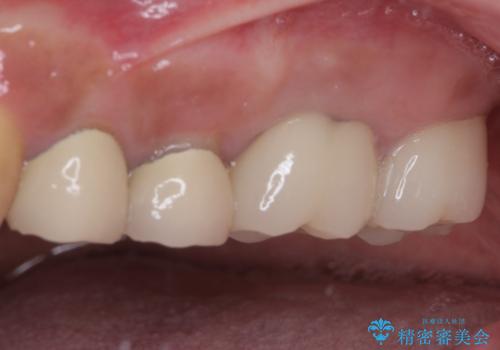

インプラントや歯周外科処置を用いた奥歯の補綴治療

- 下顎の左右奥歯が痛みがあり、噛めないとのことで来院された患者様です。

左右ともに歯根が破折しており、抜歯が必要であったため、抜歯後にインプラント補綴治療を行うこととしました。

左上は当初治療予定ではありませんでしたが、クラウンの周りに汚れがたまっていることが気になってきたため、追加して治療を行うこととしました。

歯肉縁下にまで虫歯が及んでいたため、歯冠長延長術を行い、清掃性の改善を試みます。

仮歯がない状態を極力避けたいとのことで、外科処置を少しずつ進めていくことになり、治療期間は2年間を要しました。

治療後は痛みなどなく、快適に噛めるようになりました。